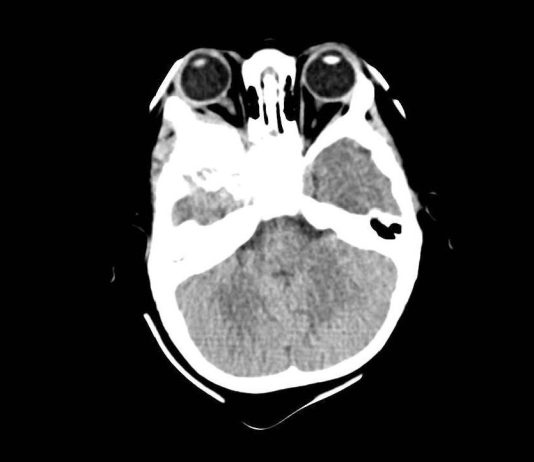

Oncologia oculare pediatrica: approccio clinico, ecografico e diagnosi differenziale in un caso di neoformazione orbitaria